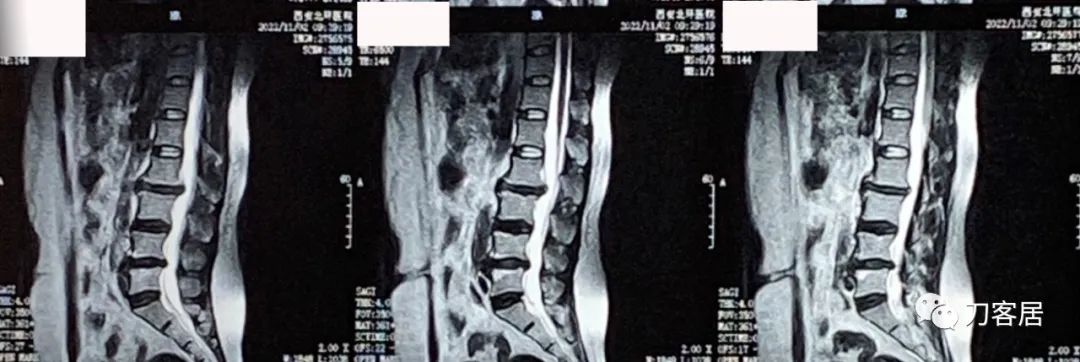

辅助检查:自带腰椎MRI提示未见严重的椎间盘突出及椎管狭窄,骨密度提示骨量减少,T值最低-1.3。

图1. 20221102西安北环医院腰椎MRI01,提示腰2-5椎间盘突出,椎体退变增生,但突出并不严重,椎管容积尚可。